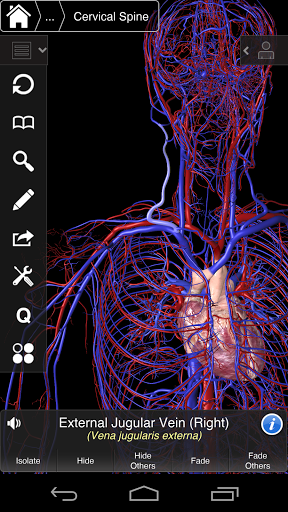

Essential Anatomy 3 representa lo último en tecnología 3D innovadora y diseño innovador. Un motor de gráficos 3D de vanguardia, creado a medida por 3D4Medical desde cero, alimenta un modelo anatómico altamente detallado y ofrece gráficos de calidad excepcional que ningún otro competidor puede lograr.

La aplicación representa un enfoque único para el aprendizaje de la anatomía general. Los gráficos no tienen paralelo y hacen que el aprendizaje, a través del uso de contenido informativo y características innovadoras, sea una experiencia rica e interesante.

⁃Veins

⁃Arteries

NUEVA TECNOLOGÍA 3D

Essential Anatomy 3 es receptivo, visualmente impactante y sin esfuerzo. La aplicación es totalmente en 3D, lo que significa que puedes ver cualquier estructura anatómica de forma aislada y desde cualquier ángulo.

---- Más de 4,000 estructuras anatómicas altamente detalladas

---- Nomenclatura latina para cada estructura anatómica